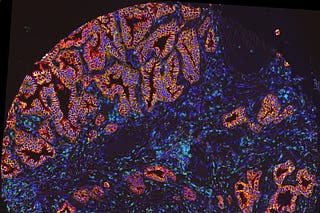

Perturb-MARS: Reading mouse experiments through a human lens

Multiplexed in-vivo perturbations, interpreted by a foundation model that has only ever seen human tumors.

TARIO-2: A Whole-Transcriptome Foundation Model from H&E Alone

Spatial transcriptomics may be the richest measurement of a tumor we have. It's also almost never collected. Here's how we get around that.